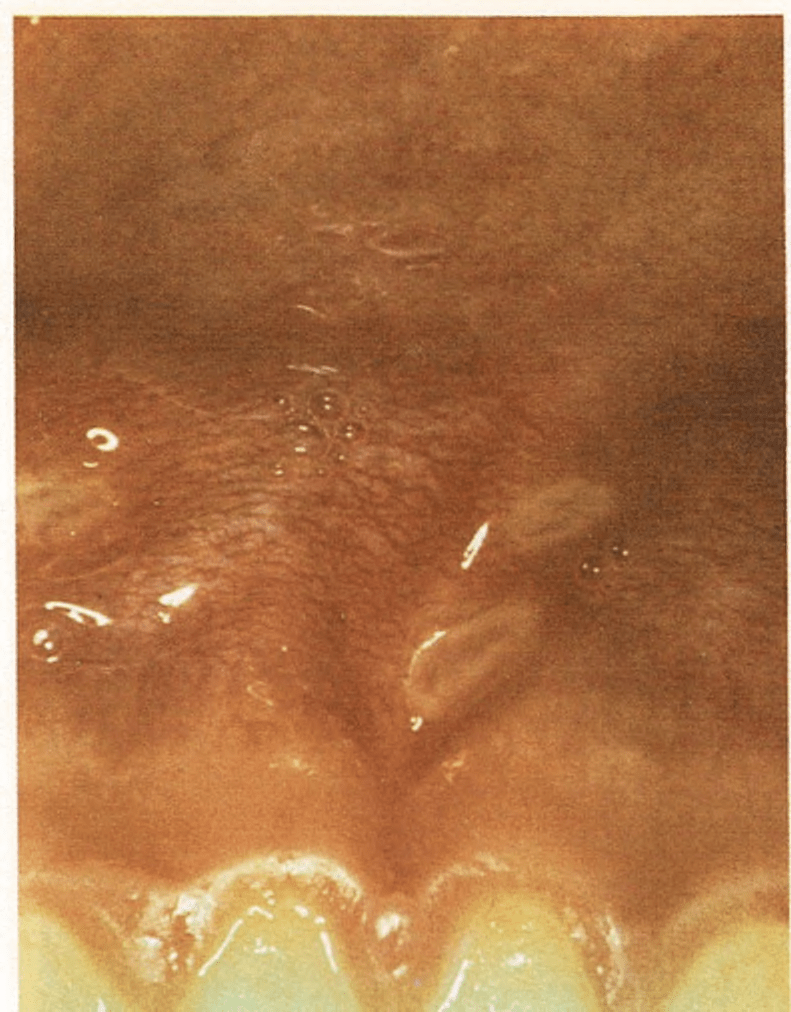

El primer síntoma lo constituyen unas pequeñas ampollas dolorosas en la parte interna de las mejillas, en la lengua o en las encías. El niño se queja de dolor de garganta y no quiere comer ni beber. Al cabo de uno o dos días, la ampolla se rompe y aparece una úlcera o llaga superficial y dolorosa.